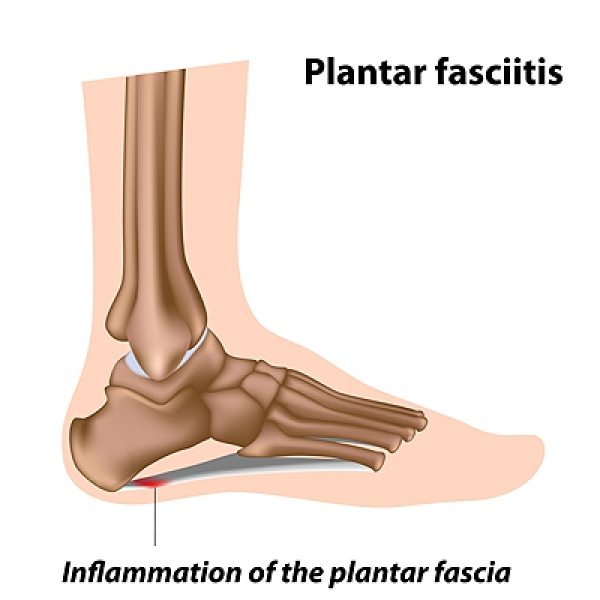

Common Conditions Causing Heel Pain

Heel Pain Causes Diagnosis Treatment

A Stabbing Heel Pain